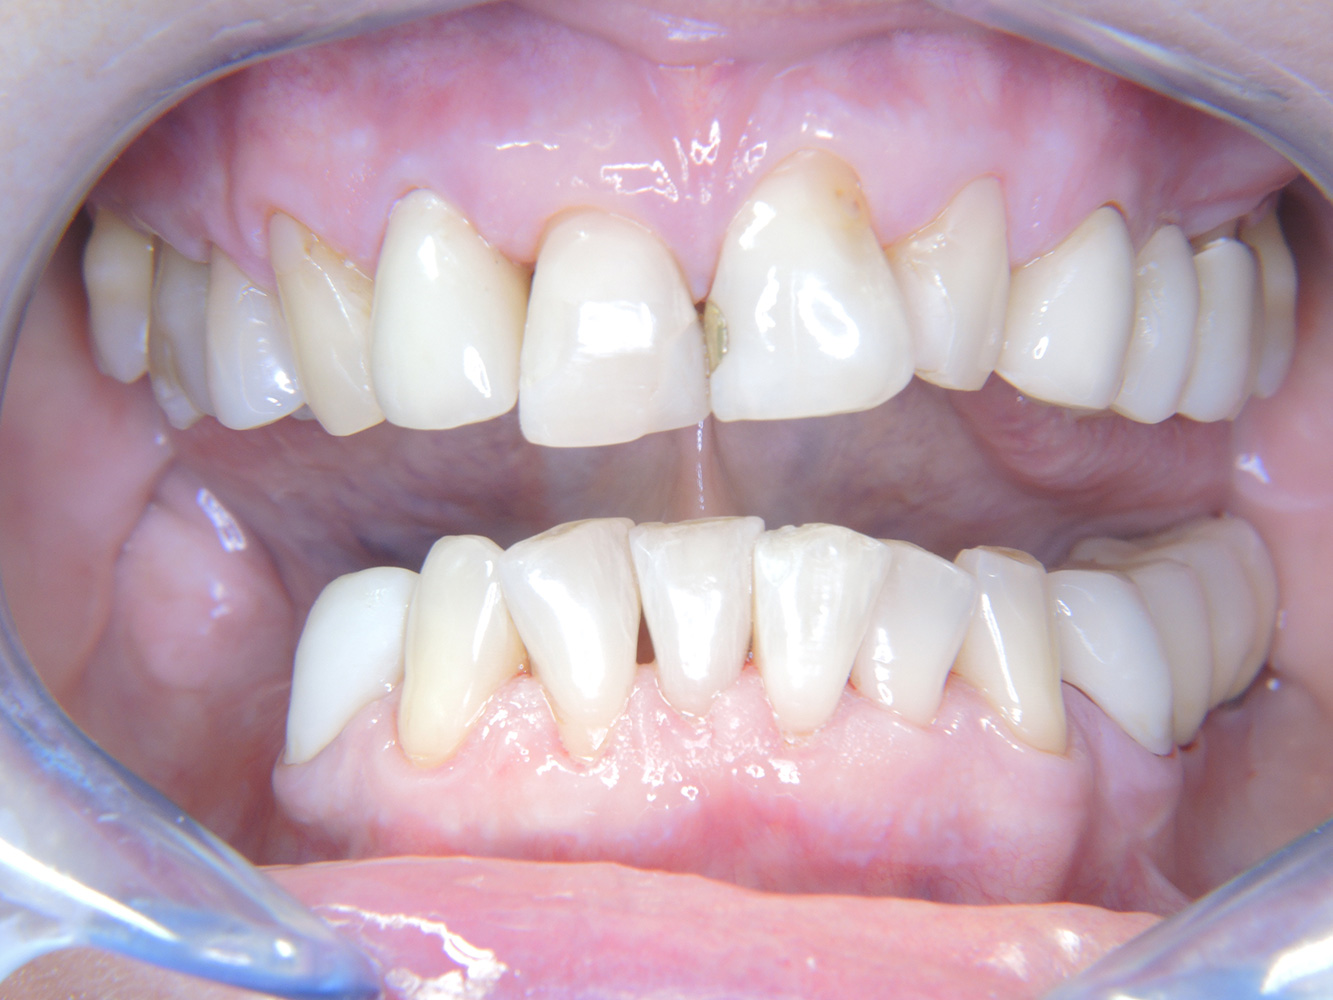

La paziente sana con precedente patologia parodontale*

Questa paziente di 68 anni non presenta alcuna patologia precedente né segue alcuna terapia che possano ritenersi rilevanti dal punto di vista odontoiatrico, e il suo stile di vita non comporta alcun rischio particolare. La paziente ha due impianti (3° quadrante, da cinque anni) e una precedente patologia parodontale (parodontite allo stadio IV, grado B) con perdita del dente. Al momento le condizioni parodontali sono stabili, tuttavia la parodontite aumenta in misura significativa le complicazioni biologiche degli impianti e c'è dunque il rischio di perdita dell'impianto (21). Per la seduta di profilassi si possono formulare quattro consigli.

Siccome la paziente non presenta alcun fattore di rischio particolare con specifiche implicazioni odontoiatriche, i bisogni rilevati dal suo attuale stato

di salute orale sono determinanti. In questo caso, si consiglia una valutazione accurata della condizione parodontale una volta l'anno. In questo modo si ha la certezza di poter intervenire in tempo qualora la precedente patologia parodontale dovesse progredire o si sviluppasse una perimplantite.